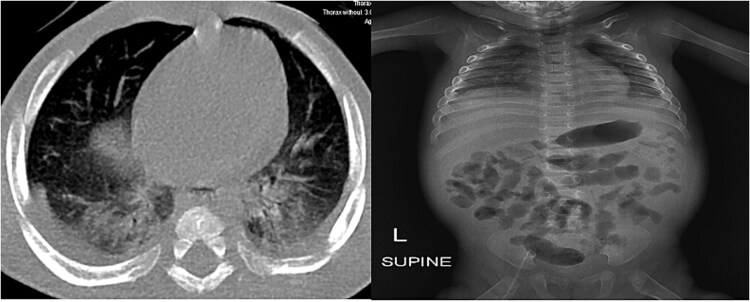

本病例报告报告了一个6个月大的男婴被诊断为婴儿全身性透明质病(ISH),并描述了诊断的困难和临床检查、实验室分析和影像学检查的结果。一例6个月大男婴因腹胀、持续性腹泻和关节压痛入院。病史包括大量水样腹泻和因低白蛋白血症住院。到达医院后,他出现了多次无血性腹泻,氧饱和度降低,以及不能茁壮成长的迹象。体格检查显示关节肿胀、痉挛、发育不全、身材矮小、发育迟缓。影像学检查包括腹部和盆腔超声显示游离液体,肠膨胀和肾微石症。影像学结果包括胸部x线片显示轻度间质标记,脑部MRI显示蛛网膜下腔扩张。实验室研究显示白细胞计数升高(13300个细胞/mm3),氨水平高,血红蛋白相对较低。最终,通过ANTXR2基因纯合子突变证实了ISH的诊断。该病例强调了对非特异性婴儿症状进行综合诊断的必要性。早期准确诊断,高度怀疑;它是任何治疗或预防并发症的基石。此外,在遗传分析的帮助下,早期识别ISH对于有效的管理和家庭咨询是重要的。这些发现增加了对ISH及其临床意义的认识,指出需要继续研究罕见的遗传疾病。

This case report presents a 6-month-old male infant with a diagnosis of infantile systemic hyalinosis (ISH) and describes the diagnostic difficulties and findings of clinical examinations, laboratory analyses, and imaging studies. A 6-month-old male infant was admitted with abdominal distension, persistent diarrhea, and joint tenderness. His history included profuse watery diarrhea and a hospitalization for hypoalbuminemia. Upon arrival, he presented with multiple episodes of non-bloody diarrhea, oxygen desaturation, and signs of failure to thrive. Physical examination revealed joint swelling, spasticity, failure to thrive, short stature and developmental delays. Imaging studies including abdominal and pelvic ultrasound showed free fluid, intestinal distension, and renal microlithiasis. Imaging results included a chest X-ray showing mild interstitial markings and a brain MRI showing dilatation of subarachnoid space. Laboratory studies demonstrated an elevated white blood cell count (13 300 cells/mm3), high levels of ammonia, and relatively low hemoglobin. Ultimately, the diagnosis of ISH was confirmed by a homozygous ANTXR2 gene mutation. This case accentuates the need for an integrated approach to the diagnosis of nonspecific infant symptoms. Diagnosis should be made early and accurately with a high index of suspicion; it forms the cornerstone for any treatment or prevention of complications. Furthermore, the early recognition of ISH is important in effective management and family counseling with the aid of genetic analysis. The findings add to the knowledge about ISH and its clinical implications, pointing to the need for continued research into rare genetic disorders.